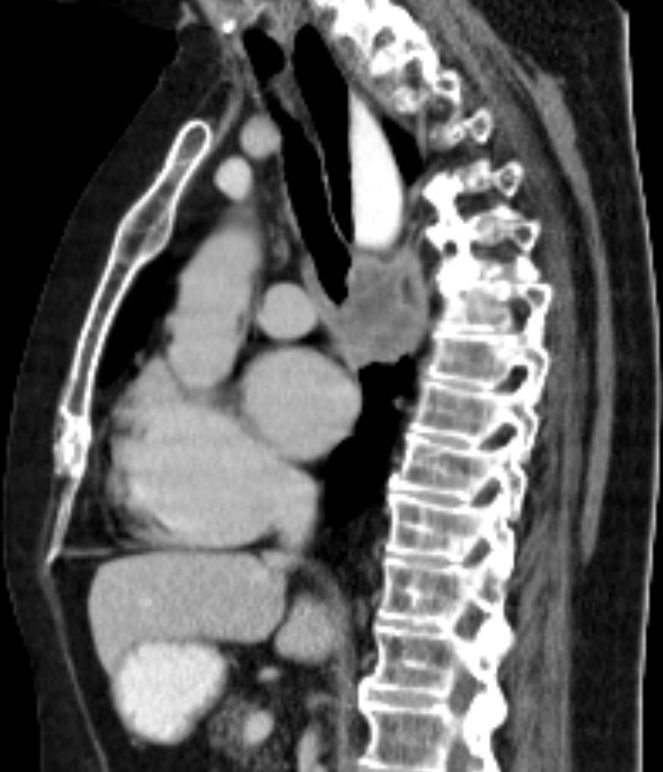

| Lunge | 58-jährige Frau, die vor 3,5 Jahren ein

Endometriumkarzinom pT2 pNo(0/33) Mo G1 hatte. 10 Monate später Pleuraerguss,

pulmonale Metastasen. Jetzt 3. Progress Carboplatin, Taxol, MPA.![]() |